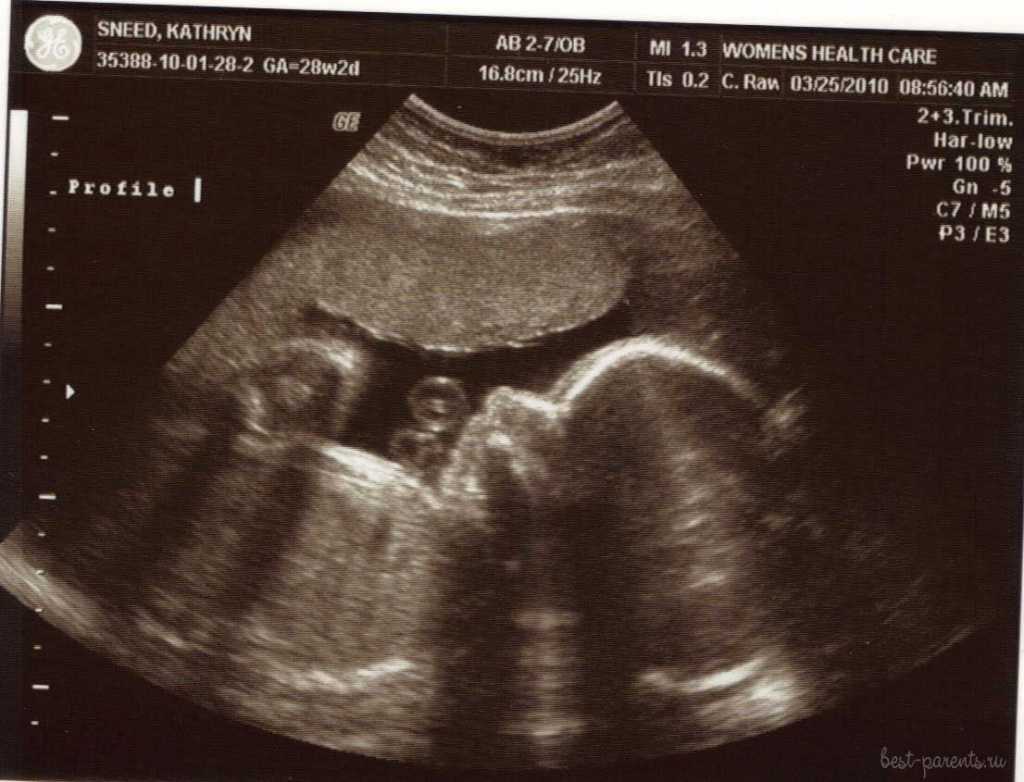

УЗИ

28 неделя беременности не требует обязательного проведения ультразвукового скрининга

При назначении этой процедуры врачом, функциональный диагност в своем описании и клиническом заключении будет обращать внимание на соответствие плода сроку вынашивания

Оценивается размер и функциональная активность внутренних органов. Определяется пол ребенка, если это не было сделано ранее

Врач обращает внимание на степень развития плаценты, ее толщину. Фиксируется количество околоплодных вод и параллельно определяется сердцебиение малыша

Плановое УЗИ на 28-й неделе беременности не проводится. Возможна выдача направления на дополнительные исследования при возникновении вопросов по состоянию здоровья матери, скорости развития плода, увеличению матки.

При желании женщина может пройти ультразвуковое исследование по собственной инициативе на платной основе для подтверждения благоприятного течения беременности.